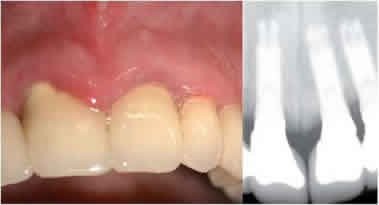

Un protocolo de mantenimiento en implantes basado en la educación

de las técnicas de higiene dental, motivación

y refuerzo llevado con rigurosidad y pautado en el tiempo e

instrumental con características especiales por parte

del profesional odontológico, determina el éxito

del tratamiento de implantes y la satisfacción de nuestros

pacientes (Figuras 10 y 11).

Figura 10. Paciente con excelente higiene y cuidados

Figura 11. Paciente con pésima higiene y cuidados